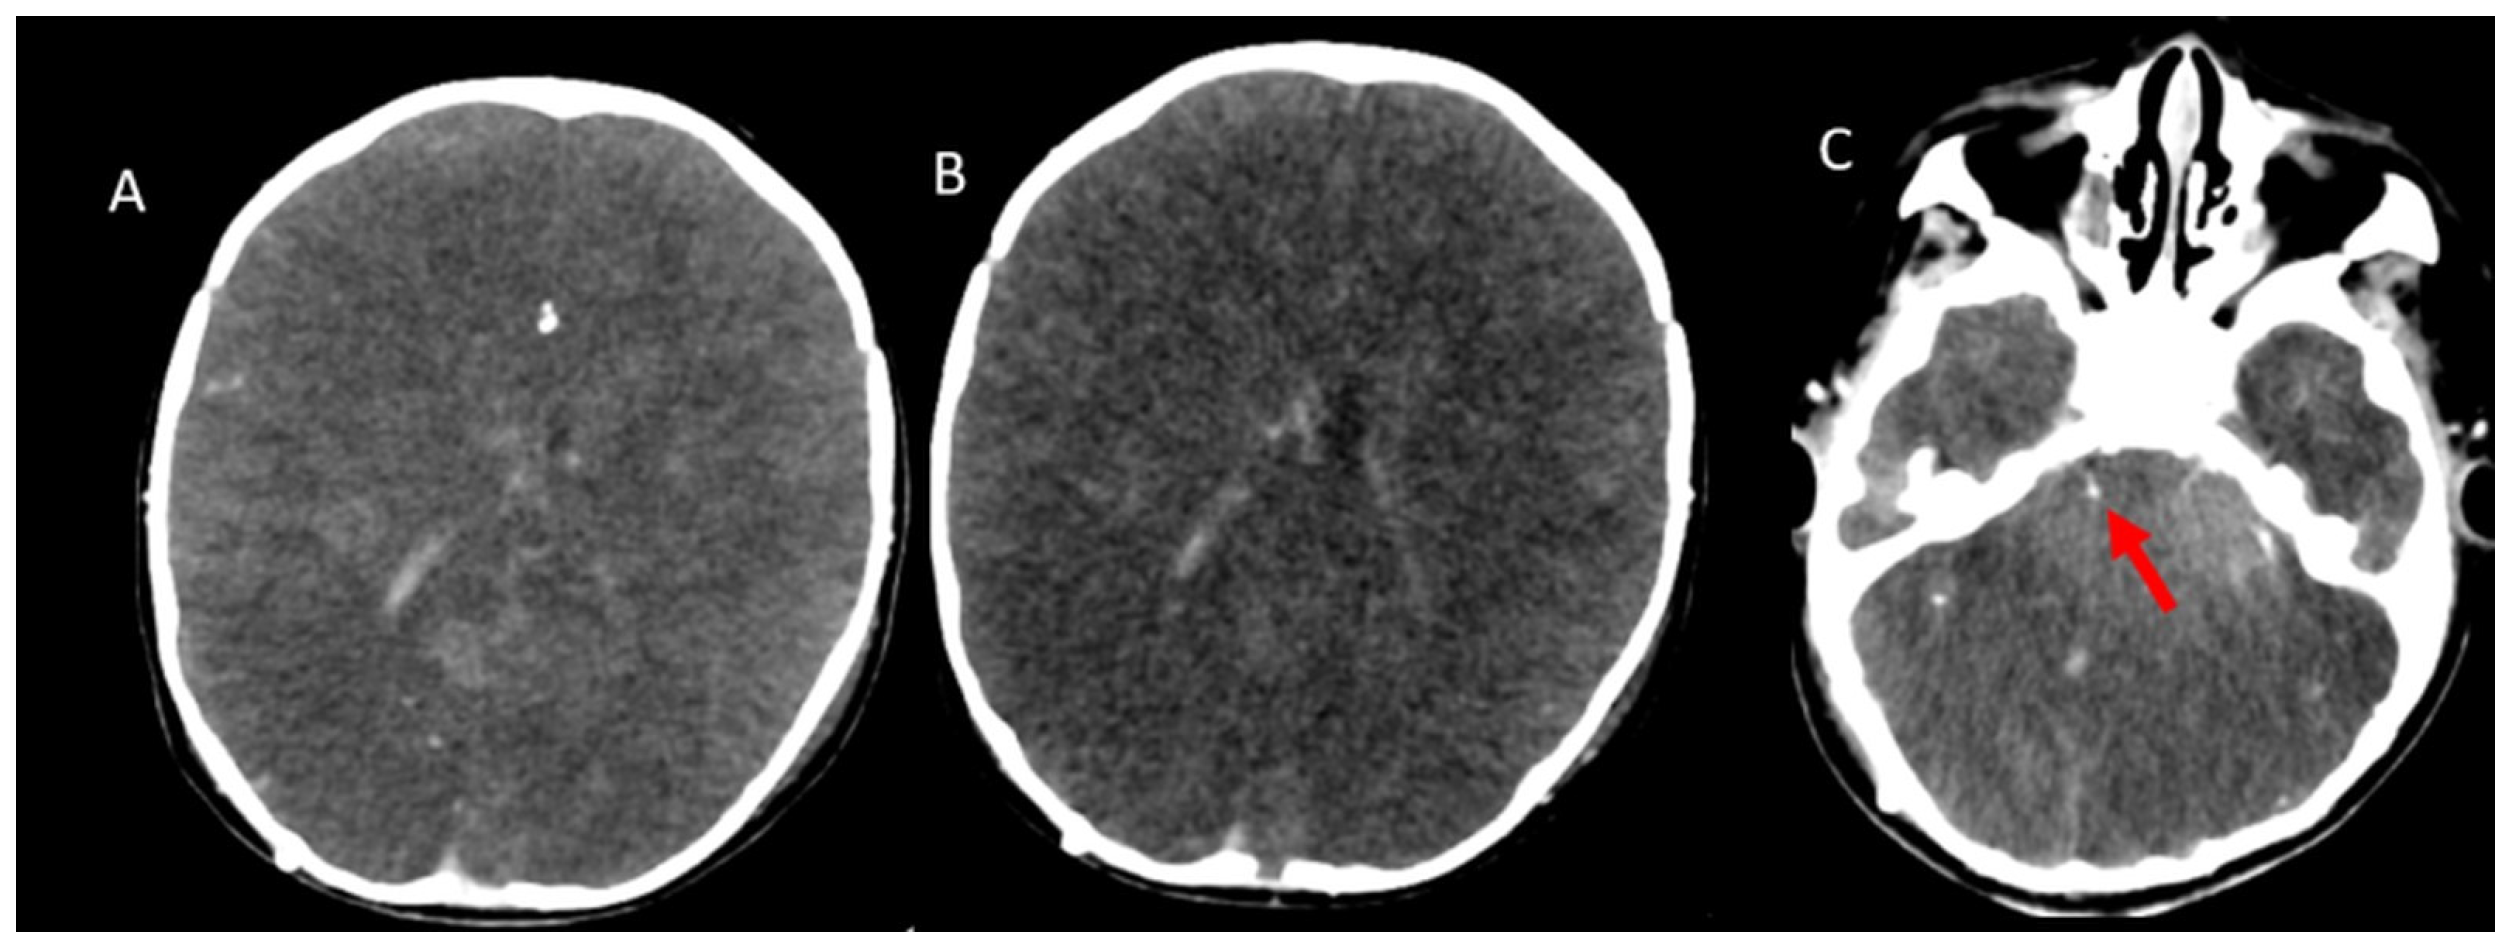

- A60-V60: Absence of opacification in M4 branches of the middle cerebral arteries (MCAs) and ICVs in the venous phase, based on the reference 4-point system by Frampas et al. [11].

- A20-V60: Absence of opacification in M4 branches of the MCAs in the arterial phase and ICVs in the venous phase, based on the revised arteriovenous scoring system by Nunes et al. [12].

- ICV-SPV: Absence of opacification in the ICVs and SPVs in the venous phase, based on the revised venous scoring system by Marchand et al. [10].

| DCE + TH | 40 (93) |

| SAH | 6 (13) |

| IVH | 10 (23.3) |